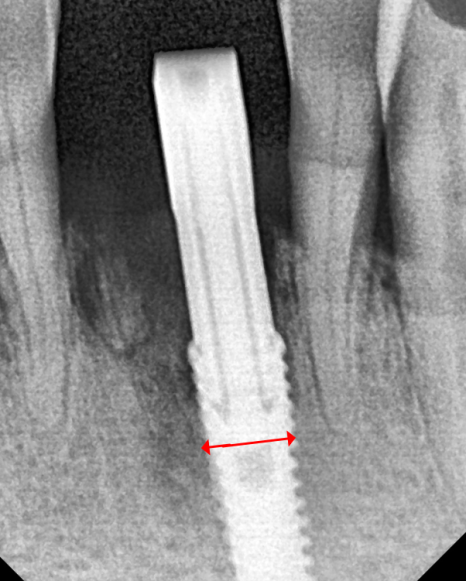

임플란트 1개로 2개를 버틴다면, 지지대는 더 든든해야 합니다.

강동구 임플란트 가격 줄이는 방법

다만 여기서 중요한

포인트가 있습니다.

임플란트를 1개만 심고

크라운을 2개로 연결하는 구조라면,

말 그대로 임플란트 뿌리(픽스처) 1개가

보철 2개를 지지해야 합니다.

그래서 이번 케이스는

일반적인 앞니용처럼

얇은 직경의 픽스처를 쓰기보다는,

직경이 더 큰 임플란트를 사용

가능한 범위 안에서

조금 더 직경이 넓은 픽스처로

계획해 안정성을 확보했습니다.

'개수는 줄이되, 지지대는 더 든든하게'

이런 방향으로 이해하시면 됩니다. ^^